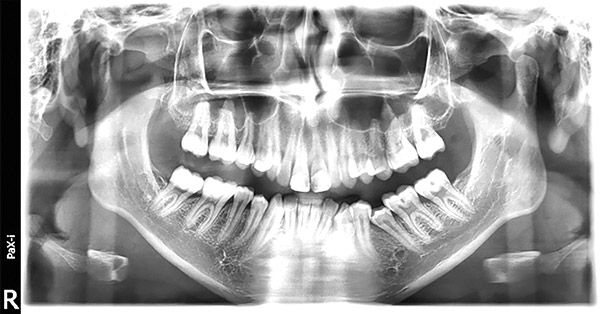

En la radiografía panorámica se observan 28 dientes permanentes presentes con el 35 en posición hacia mesial (Figura 8).

Figura 8. Radiografía panorámica.

En la radiografía panorámica, se muestra 28 dientes permanentes el correcto paralelismo radicular, la verticalización de 35 (Figura 24).

Figura 24. Rx. panorámica.